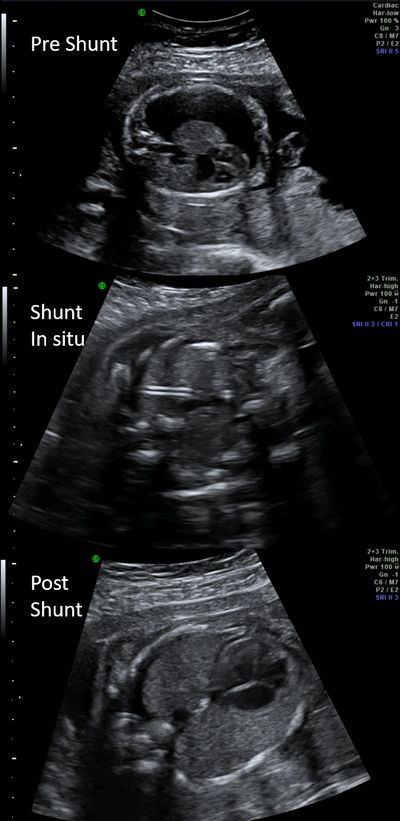

What are fetal shunts?

Fetal shunts are intrauterine procedures done as part of fetal therapy in relieving either obstruction or draining fluid within the body cavities.

As each procedure differs in technique and complexity, we shall individually discuss in detail the benefits and risks of each procedure.

Fetal Thoracic shunt for pleural effusion